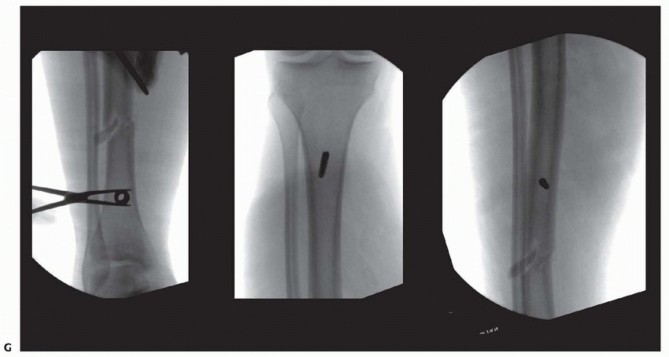

A trocar and drill sleeve are advanced directly to bone, minimizing the amount of soft tissue entrapment that might be encountered during predrilling ( TECH FIG 1C,D). A sleeve should also be used if a self-drilling pin is selected. After predrilling, an appropriate-size depth of pin is advanced by hand to achieve bicortical purchase. Any offending soft tissue tethering should be released with a small scalpel ( TECH FIG 1E,F). Fluoroscopy is used to ensure that transcortical pin placement is avoided ( TECH FIG 1G). 537

- TECH FIG 1 • (continued) G. It is important to place the trocar over the center of the medullary canal and confirm its location to ensure that the pin captures the near cortex, medullary canal, and far cortex. This confirms that a transcortical pin is avoided, as these pins can be stress risers and may lead to pin-related fracture or pin infection due to the drilling and placement in only hard, dense cortical bone.